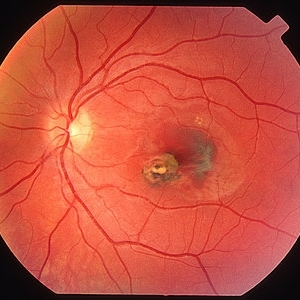

Old Presumed Ocular Histoplasmosis Syndrome

Old POHS, advanced subretinal scar formation due to CNV (end stage).